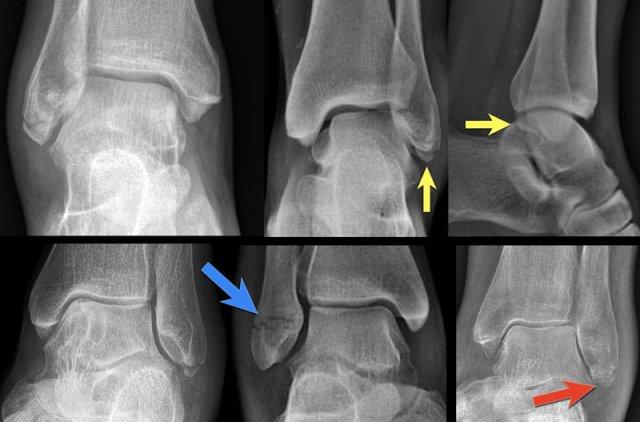

Những hình ảnh này cho thấy một gãy xương Weber B điển hình giai đoạn 4.

Có một đường gãy chéo của xương mác.

Có một gãy giật bong mắt cá sau và một gãy giật bong mắt cá trong.

Đây là một trường hợp điển hình khác của gãy xương Weber B giai đoạn 4.

Đầu tiên, hãy chú ý đến đường gãy xương mác chéo, được thấy rõ nhất trên hình chiếu nghiêng.

Đây là giai đoạn 2 và chúng ta phải giả định rằng dây chằng khớp chày mác trước đã bị đứt.

Trên hình chiếu nghiêng, có thể thấy một mảnh vỡ nhỏ của cơ mác thứ ba, cho thấy giai đoạn 3.

Bây giờ bạn bắt đầu tìm kiếm giai đoạn 4 và sẽ nhận thấy vùng thấu quang mờ ở mắt cá trong trên hình chiếu thẳng (mũi tên xanh lá).

Dựa vào hiểu biết về các giai đoạn của Lauge Hansen, đây chắc chắn phải là một đường gãy xương.

Đây là một trường hợp tinh tế hơn.

Ấn tượng đầu tiên là gãy xương Weber B giai đoạn 2.

Bây giờ chúng ta bắt đầu tìm kiếm giai đoạn 3, đó là gãy xương tertius.

Đường cản quang tuyến tính nhỏ trên phim chụp AP là đủ để chẩn đoán gãy xương tertius.

Sưng nề phần mềm ở phía trong có thể là do đứt dây chằng bên trong, tức là giai đoạn 4.